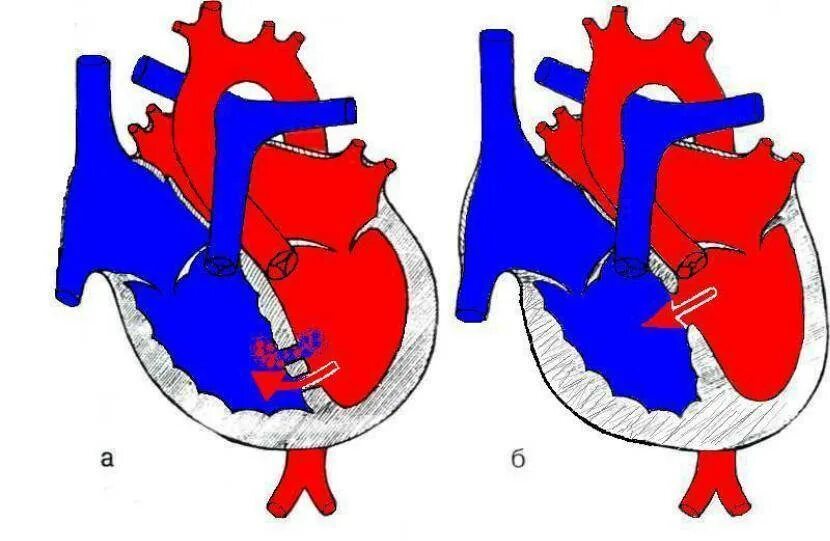

Впс дмжп у детей